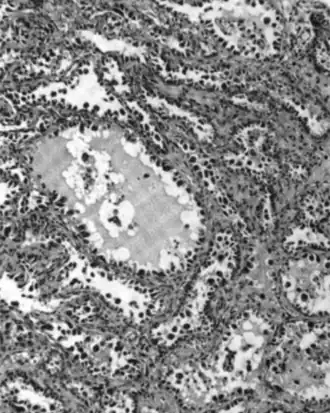

Mucinous

Mucinous tumors include mucinous adenocarcinoma and mucinous cystadenocarcinoma.[29]

Mucinous adenocarcinoma

Mucinous adenocarcinomas make up 5–10% of epithelial ovarian cancers. Histologically, they are similar to intestinal or cervical adenocarcinomas and are often actually metastases of appendiceal or colon cancers. Advanced mucinous adenocarcinomas have a poor prognosis, generally worse than serous tumors, and are often resistant to platinum chemotherapy, though they are rare.[29]